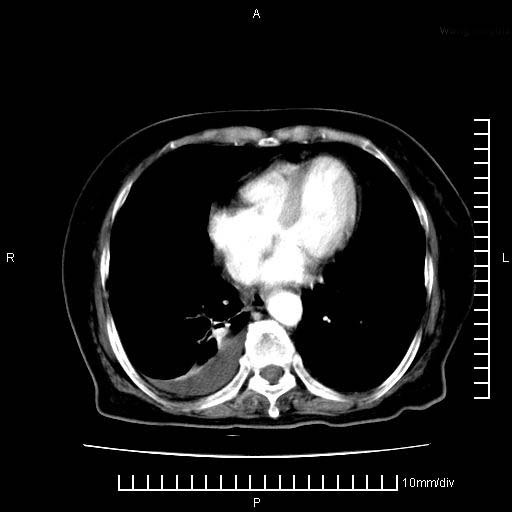

3。右胸腔积液,伴右肺下叶部分萎陷。

1)考虑胰腺癌并胰腺假性囊肿形成。2)肝内低密度灶,不排除转移。3)右肾盂积水。4)腹水。5)右侧胸腔积液并右肺下叶部分膨胀不全。

考虑胰腺ca伴腹膜腔转移、肝左叶转移、右肾积水。右胸腔积液。

考虑胰腺ca伴腹膜腔转移、肝左叶转移、右肾积水。右胸腔积液。支持